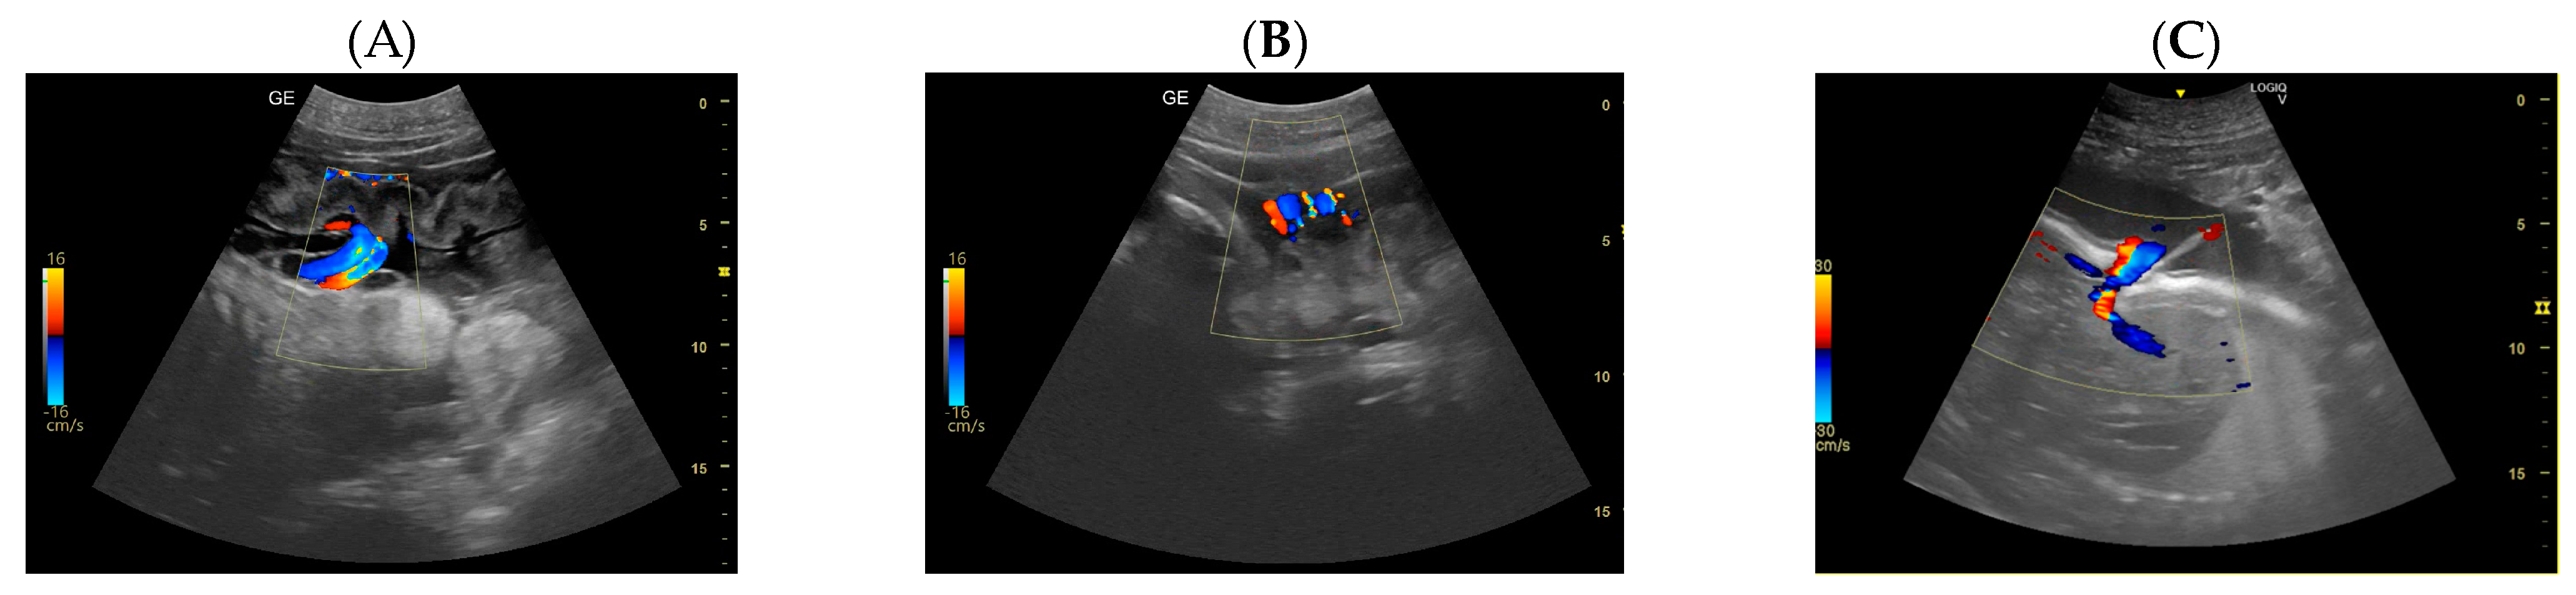

- Day 197: The umbilical cord is already seen like a hyperechoic cord form structure; it is important to identify the course, and to evaluate the internal vascular components and the absence of knots or torsions until the birth (Figure 5).